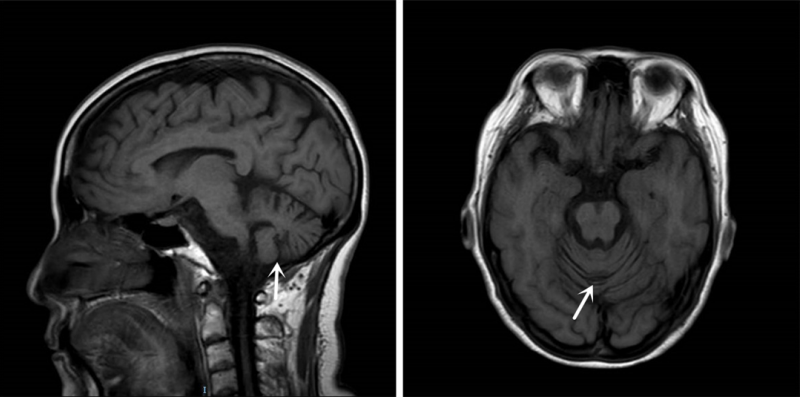

图中所示为患者萎缩的小脑

然而,她仍存在走路不稳、构音不清、头晕等症状,阎主任认为她极有可能合并神经系统疾病。经过神经科查体及追问病史并结合颅脑磁共振及肌电图检查,阎主任认为姜女士患有脊髓小脑性共济失调。此后的基因序列动态突变检查也进一步印证了阎主任的判断。